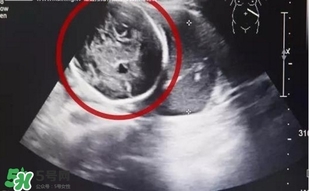

經(jīng)B超檢查,小芳竟然已經(jīng)懷孕了,而且胎兒已經(jīng)長到了6個(gè)多月!但是讓人震驚的是胎兒并沒有長在子宮里,而是長在了腹腔內(nèi)。醫(yī)生確診小芳為“腹腔妊娠”,也就是宮外孕的一種,這種發(fā)病率約為1:15000,母體死亡率約為5%,胎兒存活率僅為1%的罕見妊娠,竟然發(fā)生在了她的身上,而且小芳已經(jīng)出現(xiàn)肚子疼痛,情況十分緊急!